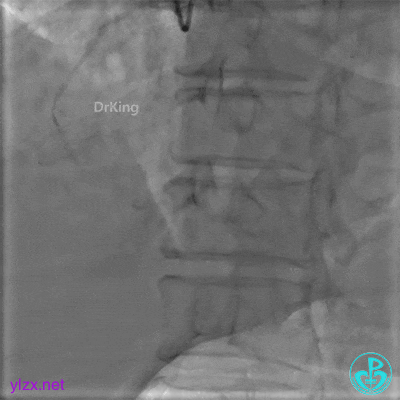

微导管送入PL分支远段,取明胶海绵颗粒栓塞剂1ml通过微导管向远端血管推注栓塞远端血管。

封堵后造影,PL分支远端血流中断。

心包内无明显积液。